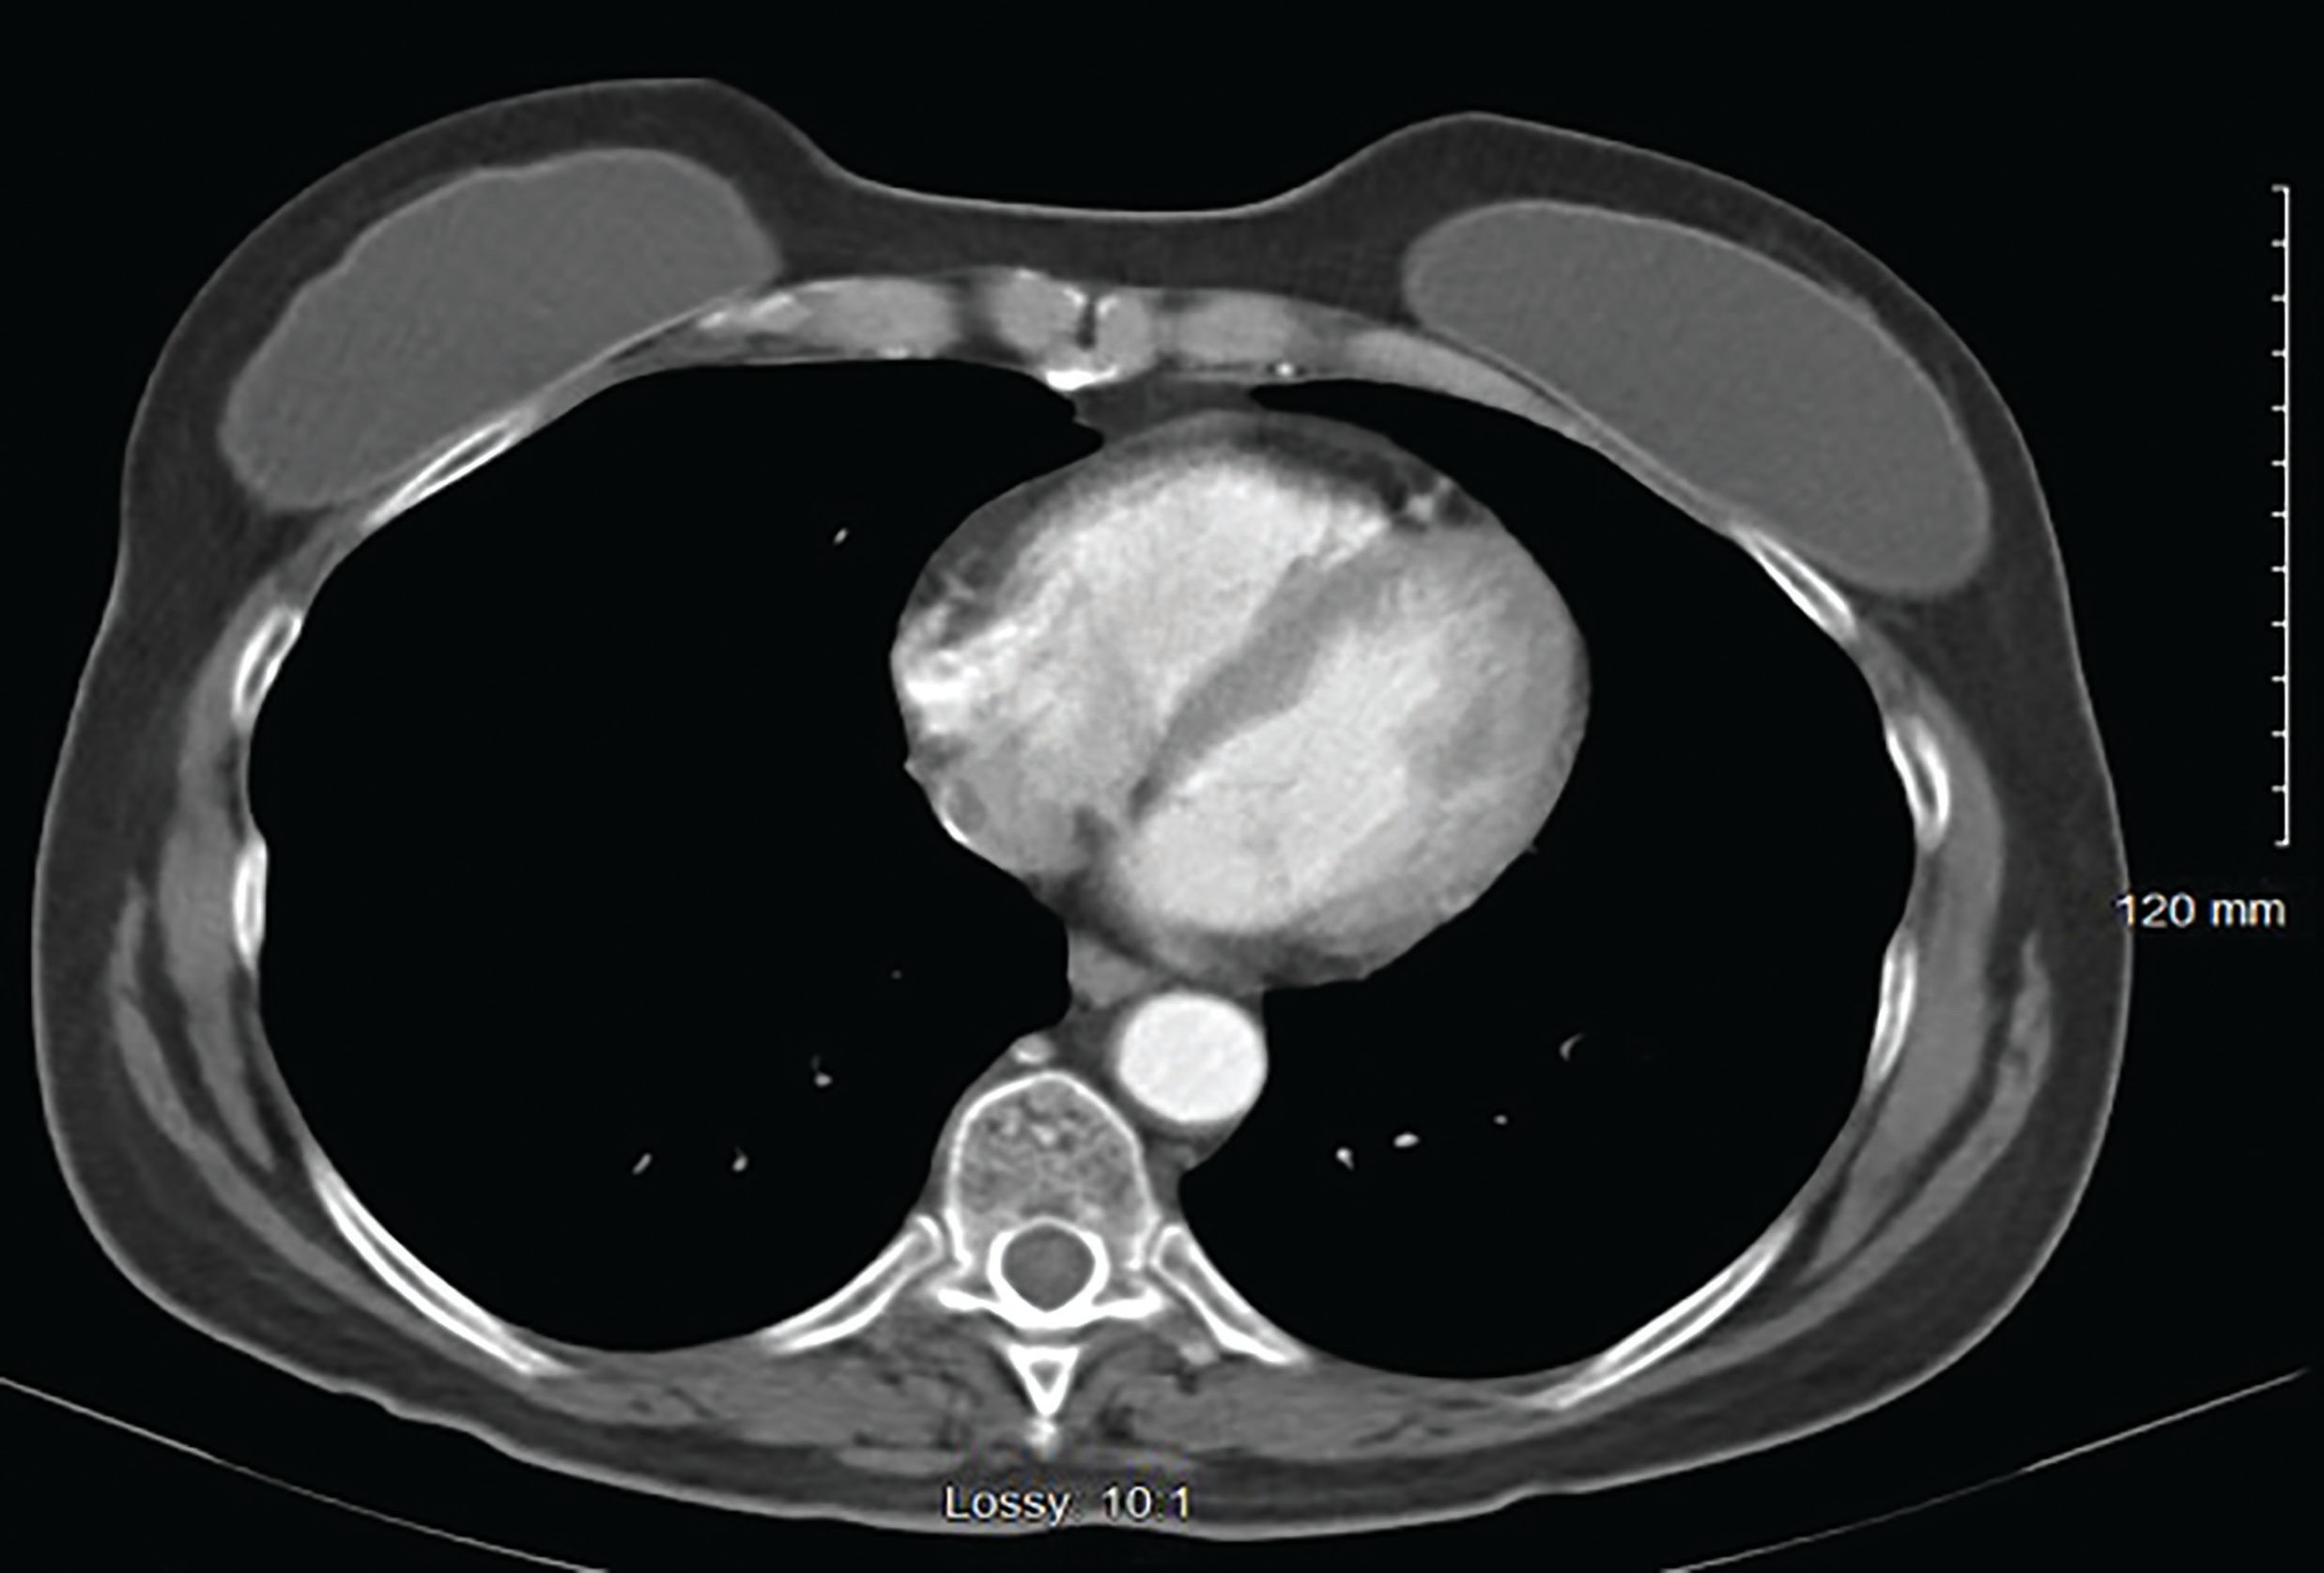

患者10年前接受过双侧硅胶乳房植入,并且1年前确诊为局限期小细胞肺癌,接受依托泊苷/顺铂联合胸壁放疗治疗后完全缓解。通过CT评估此皮肤结节时,并对其进行了超声引导活检。胸部CT证实了双侧乳房植入物的存在,右乳房中下部象限中有一个1.8cm的乳腺结节,并且存在一个右腋窝淋巴结(图2)。

图2